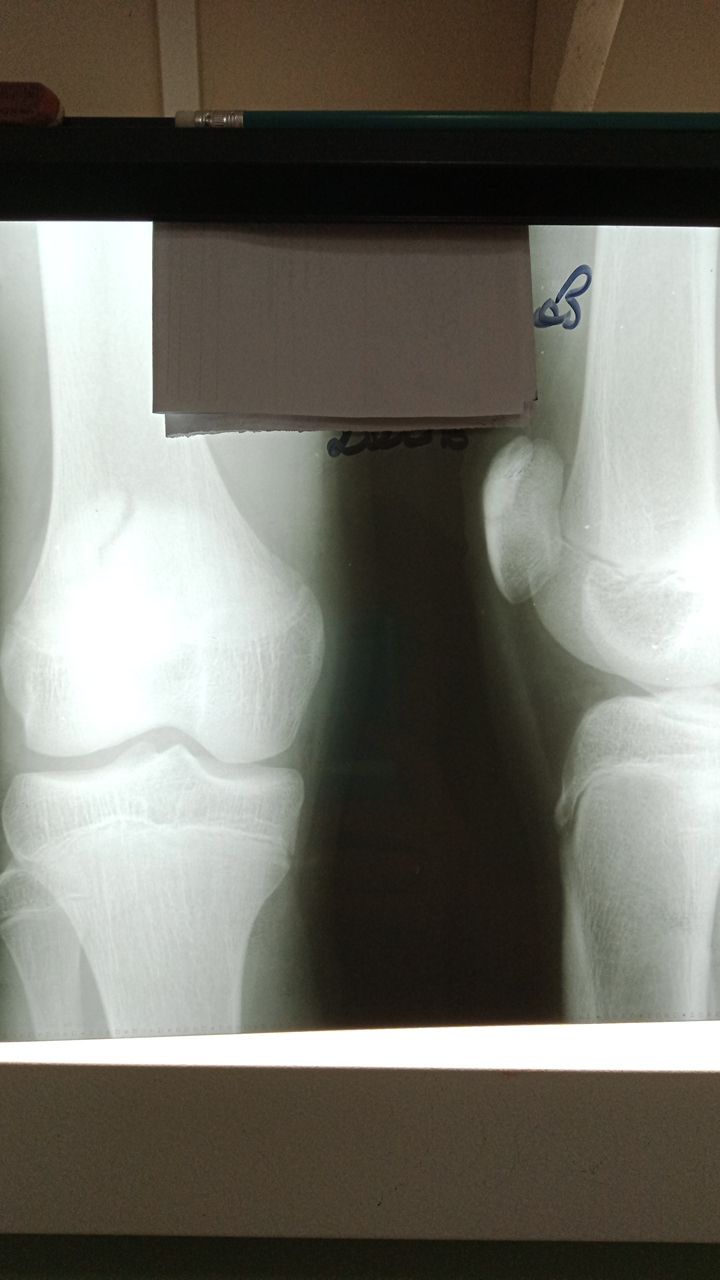

Здравствуйте. Ребенок 2006г. Травмы отрицает. Остеохондропатия надколенника справа? Слева норма.

Я за patella bipartita